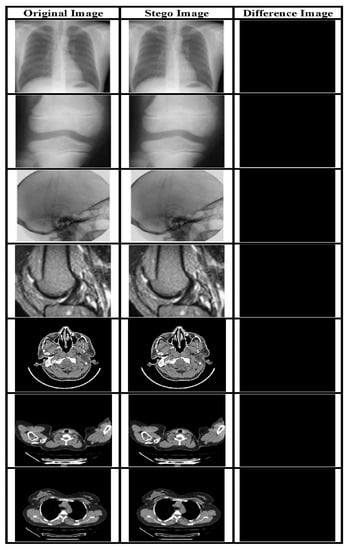

The payload is a critical underlying requirement of a data hiding system. The perceptual quality of the SI is evaluated using subjective and quality metrics like PSNR and it is a direct function of payload. In our proposed system we have embedded two types of data in the CI obtained using a novel IP method: EHR and watermark. Both types have been embedded using the LSB approach. The visual quality of the SI yielded by the embedding method is evaluated based on objective as well as subjective analysis. Figure 5 presents various original and Stego-MIs with a payload value equal to 0.75 bpp. The generated SI’s quality is much superior, along with high payload value. Furthermore, to validate the described RDH method a comparison has been made with contemporary works mentioned in [44] as shown in Figure 6 and Figure 7.

Figure 5.

MI with their corresponding SI for a payload of 0.75 bpp and the subtracted image.

The value of avg. PSNR for MI is 52.3756 dB whereas the avg. SSIM is 0.9849. This indicates that the scheme can yield high-quality images with a considerably high payload.

The PSNR2 and SSIM2 value for SI and the said payload is illustrated in Table 3.